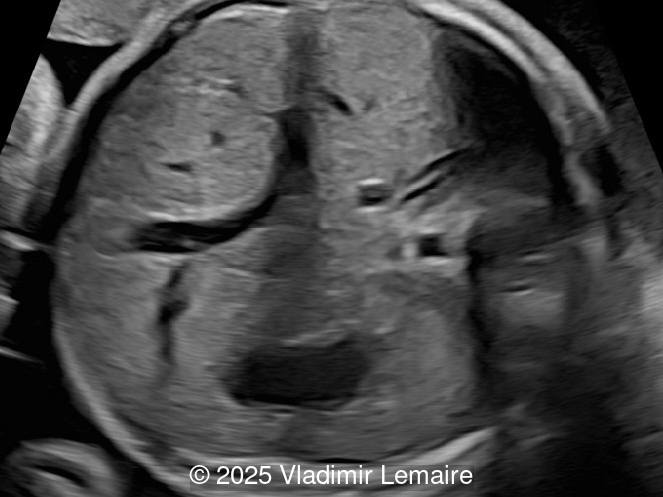

- Image 1: Transverse view of the upper abdomen at the level of the abdominal circumference.